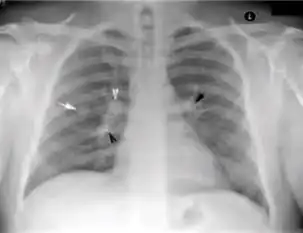

Chest X-ray

Tuberculosis creates cavities visible in x-rays like this one in the patient's right upper lobe.

A posterior-anterior (PA) chest X-ray is the standard view used; other views (lateral or lordotic) or CT scans may be necessary.

In active pulmonary TB, infiltrates or consolidations and/or cavities are often seen in the upper lungs with or without mediastinal or hilar lymphadenopathy.[1] However, lesions may appear anywhere in the lungs. In HIV and other immunosuppressed persons, any abnormality may indicate TB or the chest X-ray may even appear entirely normal.[1]